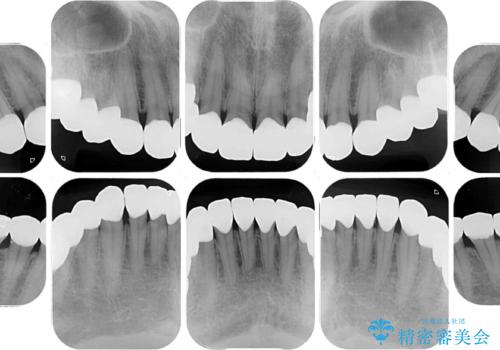

- 奥歯の銀歯をセラミックにしたいとのことで来院された患者様です。

当初は奥歯のみの治療をご希望でしたが、話を進めていくうちに、軽度ではあるものの、幼少期の薬の影響で歯が変色していることがコンプレックスであるということが分かりました。

長年歯の色が塞ぎ込んでいた部分があるとのことで、これを機会に全ての歯を真っ白にするために、オールセラミッククラウンにて補綴治療を行うこととしました。

より白さが目立つように、自然な仕上がりではなく、作り物の雰囲気があるフルジルコニアクラウンにて補綴治療を行いました。